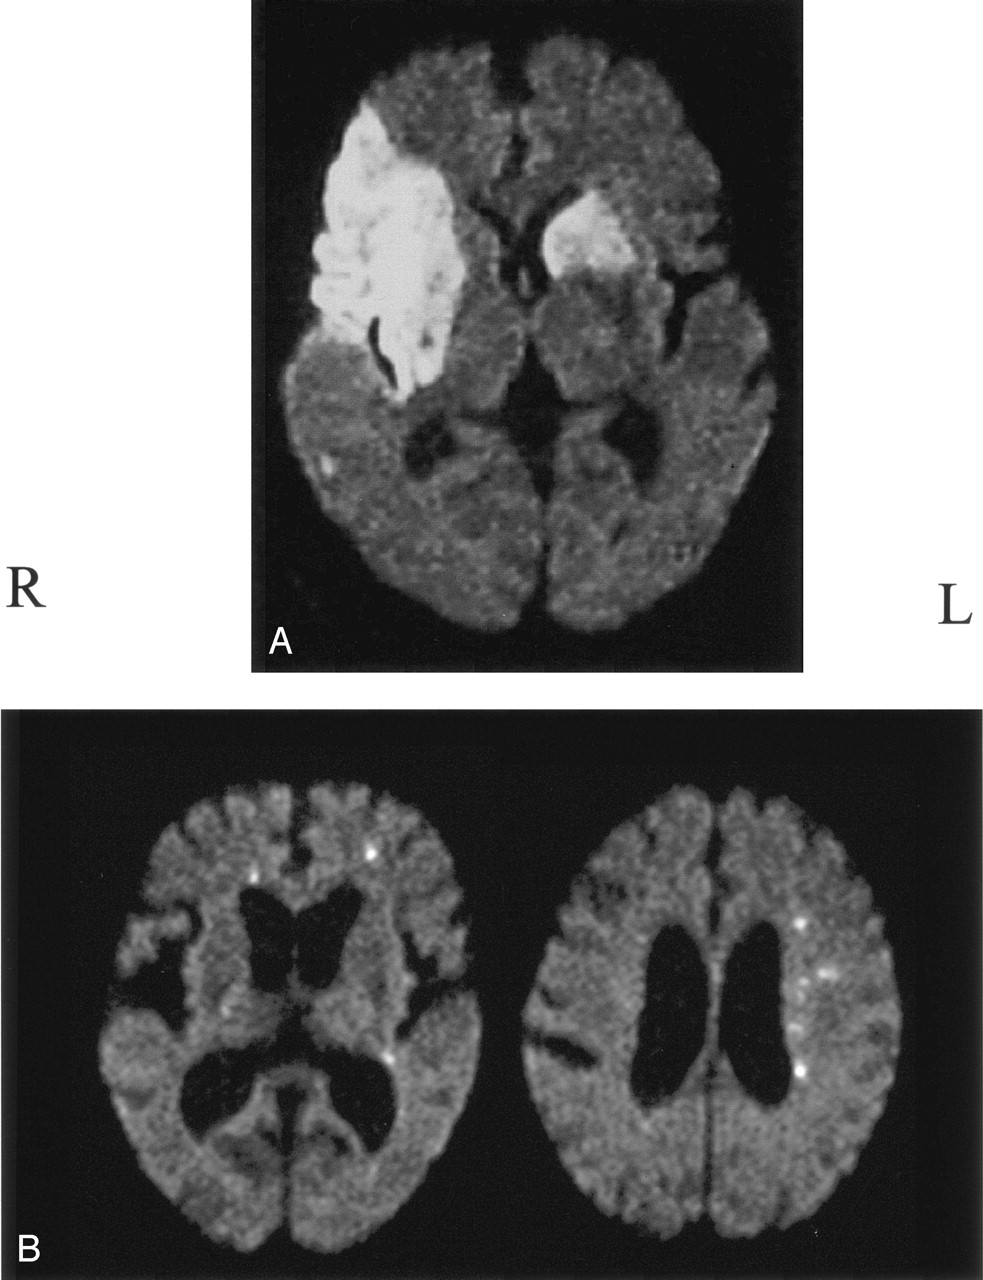

Modifying earlier methods ( 13, 17–19) based on the volume and distribution pattern of the hyperintense area on DWI, we classified infarctions into three types: 1) territorial infarction more than 15 mm in diameter, including more than one infarct with a continuous lesion from the cortex to the subcortex (Fig 1A, right side); 2) subcortical infarction more than 15 mm in diameter in the territory of deep perforating branches originating from the distal ICA or the MCA trunk (Fig 1A); and 3) disseminated small infarction less than 15 mm in diameter (Fig 1B). On the basis of the total volume of hyperintense areas on DWI, we defined the hemisphere with larger volume of the infarcts as the predominantly affected hemisphere, and that with the smaller volume was the subordinately affected hemisphere (Fig 1). The lesions were classified in blinded fashion with regard to the results of source identification, and vice versa.

Classification of infarction.

A, Right-sided infarction was defined as territorial; left sided, subcortical. Total volume of the infarcts was smaller on the left than right, which was defined as the predominantly affected hemisphere.

B, DWI shows small disseminated lesions. The predominantly affected hemisphere is the left side, and infarcts on the contralateral side are localized in the ACA area.